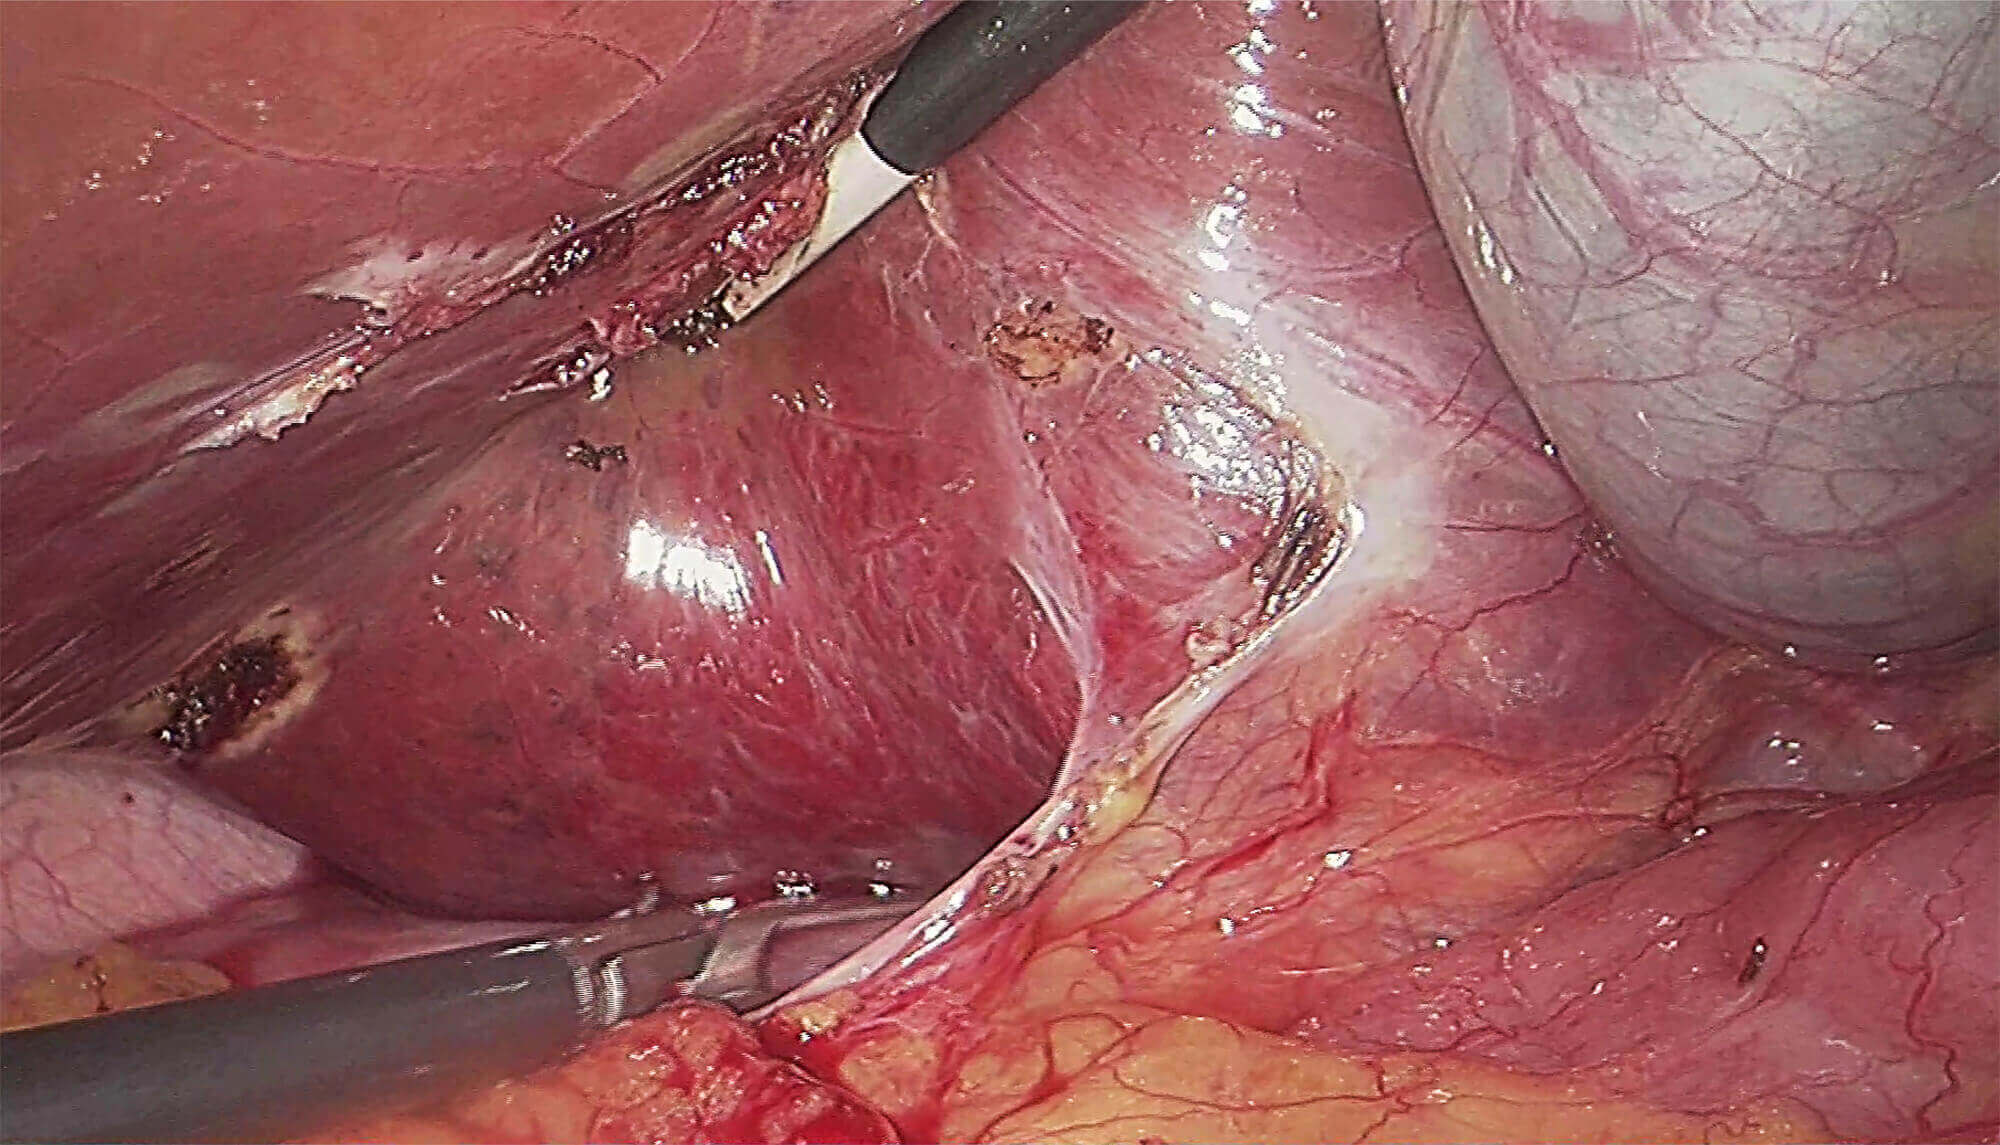

采用3片CMOS图像传感器,输出1920*1080P、60FPS全高清数字信号,提供稳定的腔镜视野,给予术者极佳的视觉体验,让手术更轻松,更精细!

是一种基于血红蛋白对不同波长光吸收系数不同的原理而设计的智能染色成像系统,兼有电子染色和光学染色功能,能够凸显粘膜血管结构,有助于病灶部位识别和诊断,为临床医生术中判断提供参考信息。

光电复合染色成像